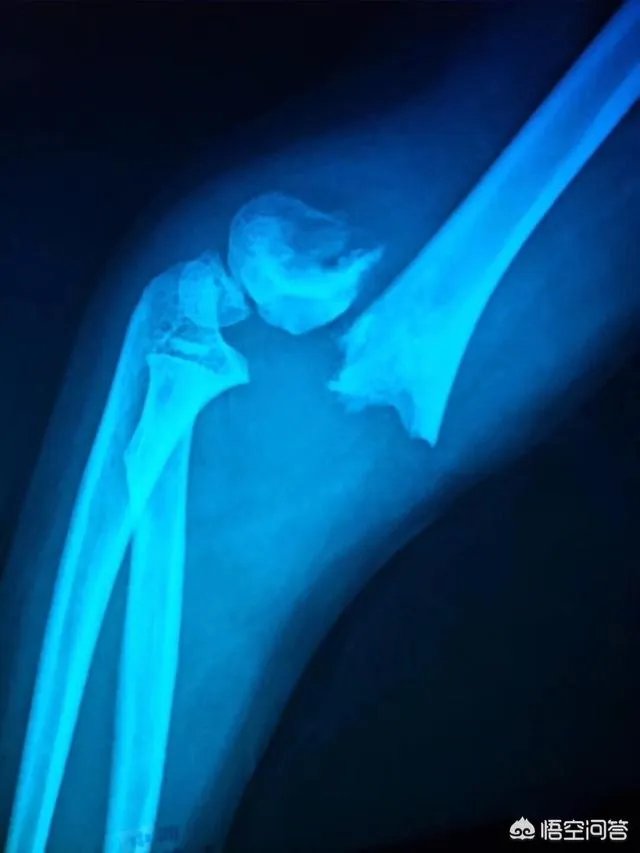

这事发生在成都青羊区的一家幼儿园,小女童送医院的时候,胳膊是S形的。那为什么说老师报复呢,起因是摔伤的前一天,小女童在课堂上和同桌讲话,惹老师生气了,小女童说,老师不准她玩玩具,还打了她嘴巴。这事到现在,小女童还没有完全康复,家长要求调监控,园方回应称,监控被老鼠咬断,拒绝了家长的赔偿要求。这事我认为如果园方不能举证其尽到了管理职责,则难辞其咎,应当承担赔偿责任,建议家长和园方协商解决,协商解决不成的,可以向教育主管部门反映情况,通过行政调处方式予以解决,或者直接向法院提起诉讼。

胳膊呈“S”型,无论是人为原因还是外力所致,这种伤都可以进行医学鉴定,进行医学鉴定的前提是医学鉴定机构必须客观、公正。

事发前一天,小女孩告诉妈妈:自己在课堂上和同学讲话,惹老师生气了,老师不准她玩玩具,还打了嘴巴。

第二天一大早,小女孩妈妈就对于此事向校长反映了情况,10点多小女孩就出事了,暂且不说两者有什么关联,但是事情的蹊跷程度不禁让人汗颜。

其次关于孩子在幼儿园胳膊骨折的事情。情况已经属于比较严重。不管是不是园所有报复举动,这样的情况也已经属于幼儿园的监护不力,因为家长把孩子送到幼儿园,幼儿园就应该履行好自己的看护照顾的职责。针对孩子的胳膊骨折,如果幼儿园置之不理或是推卸责任,家长可找到上级当地的教育部门或机构。